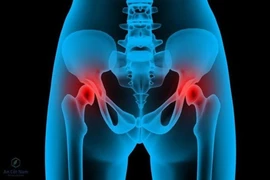

(khoahocdoisong.vn) - Hoại tử vô khuẩn chỏm xương đùi là tình trạng chỏm xương đùi bị phá hủy mà nguyên nhân là do thiếu nuôi dưỡng. Nguyên nhân gây bệnh có thể do chấn thương của khớp háng (gãy cổ xương đùi, trật khớp háng...), uống nhiều rượu, hút nhiều thuốc lá, lạm dụng corticoid, bệnh lý mạn tính toàn thân...

Trật khớp háng bẩm sinh là một bệnh lý nguy hiểm song lại khó phát hiện sớm khi trẻ mới chào đời. Nếu được phát hiện sớm trước 6 tháng tuổi điều trị đơn giản, nhưng đa phần trẻ biết đi mới được phát hiện nên gây nhiều di chứng.

(khoahocdoisong.vn) - Để phẫu thuật thay khớp háng không chỉ căn cứ vào phim X-quang mà cần căn cứ vào triệu chứng (đặc biệt là triệu chứng đau), lứa tuổi và sau đó là điều kiện tài chính của bệnh nhân.